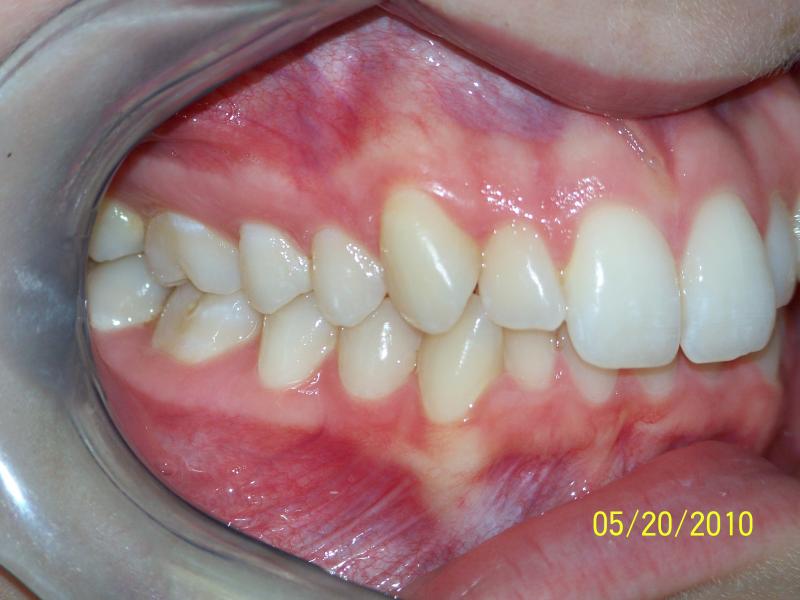

Isabelle G.

Invisalign Case

INVISALIGN, 10 months, 1 series of aligners to correct alignment, deep overbite and shift teeth to the right to match upper and lower mid line, TOTAL TREATMENT TIME: 10 months COSMETIC DENTISTRY: incisal reduction of anterior teeth before and after Invisalign.

Deep Overbite, Teeth Reshaping, Testimonial